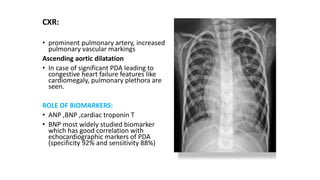

CXR:

• prominent pulmonary artery, increased

pulmonary vascular markings

Ascending aortic dilatation

• In case of significant PDA leading to

congestive heart failure features like

cardiomegaly, pulmonary plethora are

seen.

ROLE OF BIOMARKERS:

• ANP ,BNP ,cardiac troponin T

• BNP most widely studied biomarker

which has good correlation with

echocardiographic markers of PDA

(specificity 92% and sensitivity 88%)